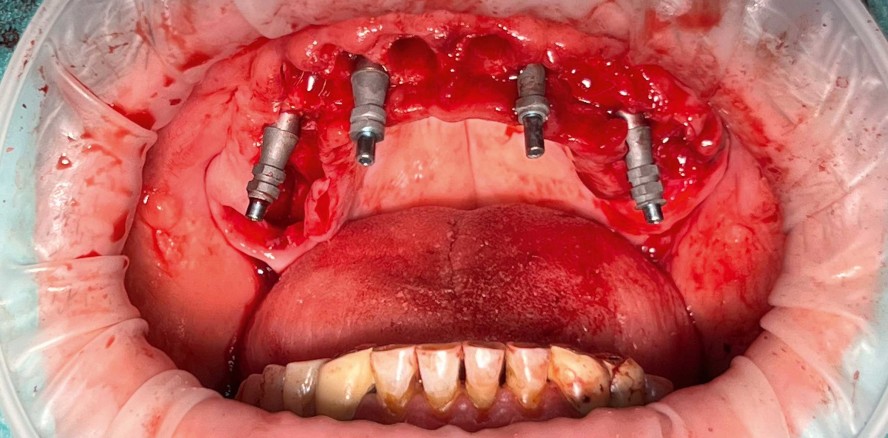

Foto: © Praxisklinik Herne & Zahnarzt Dr. Rüdiger Mintert

Dr. Rüdiger Mintert: Von den heutigen Möglichkeiten einer sofortigen Versorgung und Belastung von einzelnen Zähnen sowie Brücken bis zu All-on-4 hat es insbesondere im letzten Jahrzehnt einen gewaltigen Sprung in diesem Bereich gegeben. Dies wird durch die ständig fortschreitende Rechenleistung erreicht, die es ermöglicht, komplexe Eingriffe derart präzise vorauszuplanen, dass Patienten innerhalb kürzester Zeit oral rehabilitiert werden können. Dabei spielt es kaum noch eine Rolle, wie ausgedehnt die zu versorgenden Areale sind. Minimalinvasiv ist heute daher eher ein Synonym für eine „verkürzte“ Behandlungszeit. Die ursprüngliche Begrifflichkeit, ähnlich „wie durch ein Schlüsselloch“ zu operieren, rückt hier sicherlich in den Hintergrund. Die dafür erforderlichen Schablonentechniken sind heute auch durch die Vielzahl von Herstellern und Kompatibilität mit nahezu jedem Implantatsystem verfügbar. Auch Operateure, die über weniger AusbildungsKnow-how verfügen, werden in die Lage versetzt, komplexere Eingriffe über den Service der verschiedensten Anbieter planen zu lassen. Somit wird einer immer breiteren Masse von Patienten heute der Zugang zu Implantatoperationen ermöglicht, die früher nur von sehr spezialisierten Chirurgen durchgeführt wurden. Für die Patienten bedeutet Implantologie heute nicht nur minimalinvasiv, sondern dadurch vor allem schnellstmöglich zum erhofften Behandlungsziel zu kommen – am besten am gleichen Tag.

Es bedarf einer genauen Analyse von knöchernen und Weichgewebestrukturen, die einen operativen Eingriff auf das bestmögliche chirurgische Vorgehen optimieren. Dazu zählen die Kenntnisse der chirurgischen Verfahren, der Möglichkeiten biologischer Unterstützung durch I-PRF, A-PRF oder Tunneltechniken, die heute auch in der Parodontologie extrem gewebeschonende Eingriffe ermöglichen. Insbesondere die Nutzung der modernen radiologischen Unterstützung durch die DVT-gestützte Analyse aller Strukturen macht es erst möglich, den Aufwand und das Risiko von Eingriffen so minimal wie möglich zu gestalten. Dabei hat sich in der Implantologie die Anwendung von den ursprünglichen Orientierungsschablonen zu den Full-guided-Schablonen bei erfolgtem Backward Planning als Goldstandard etabliert. Mit einer schablonengeführten Operation kann die Planung maximal sicher, zeitsparend, schonend und somit minimalinvasiv durchgeführt werden. Weitergehend hat sich alles aus dem zahntechnischen CAD/CAM-Bereich angeschlossen, was als Nebeneffekt auch die Sofortversorgung bei Zahnextraktion und die Sofortbelastung ermöglicht. Der komplette Workflow eines operativ parodontologischen, implantologischen und prothetischen Vorgehens kann heute so komplett im Vorfeld digital abgebildet werden.